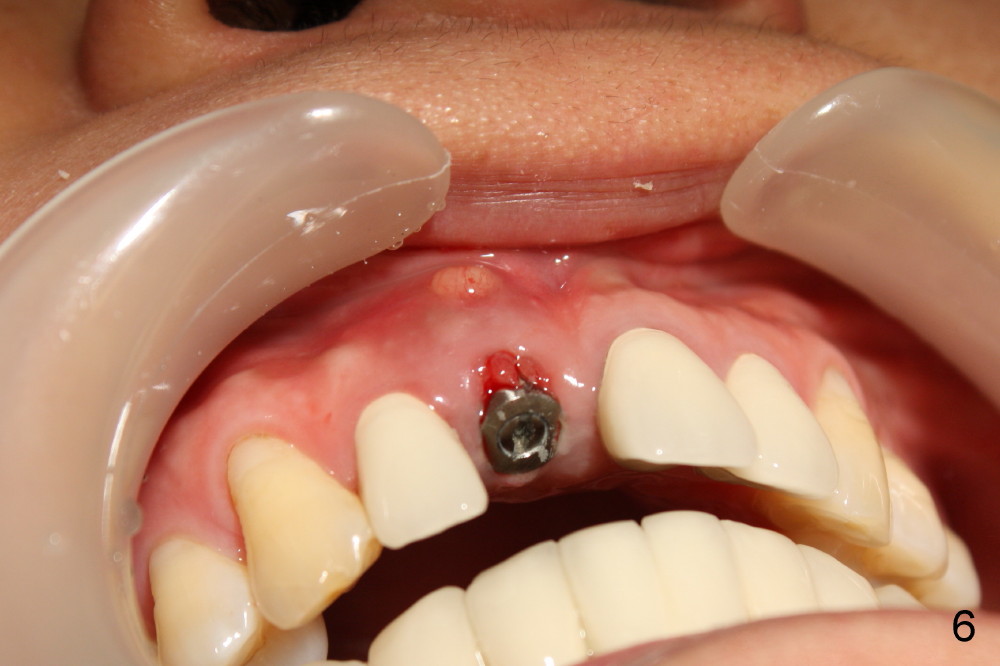

Sixteen days after surgery, the patient returned with chief complaint "I do not have pain, but there is a swelling".  Exam shows that there is localized apical swelling with + fluctuance (Fig.4: *) and granulation tissue at gingival margin (>).  Under local anesthesia, I & D is performed with sanguine exudate, buccal apical plate perforation with implant threads exposed.  Tetracycline normal saline is used for irrigation.  The patient was asked to return every 1-2 days for irrigation.